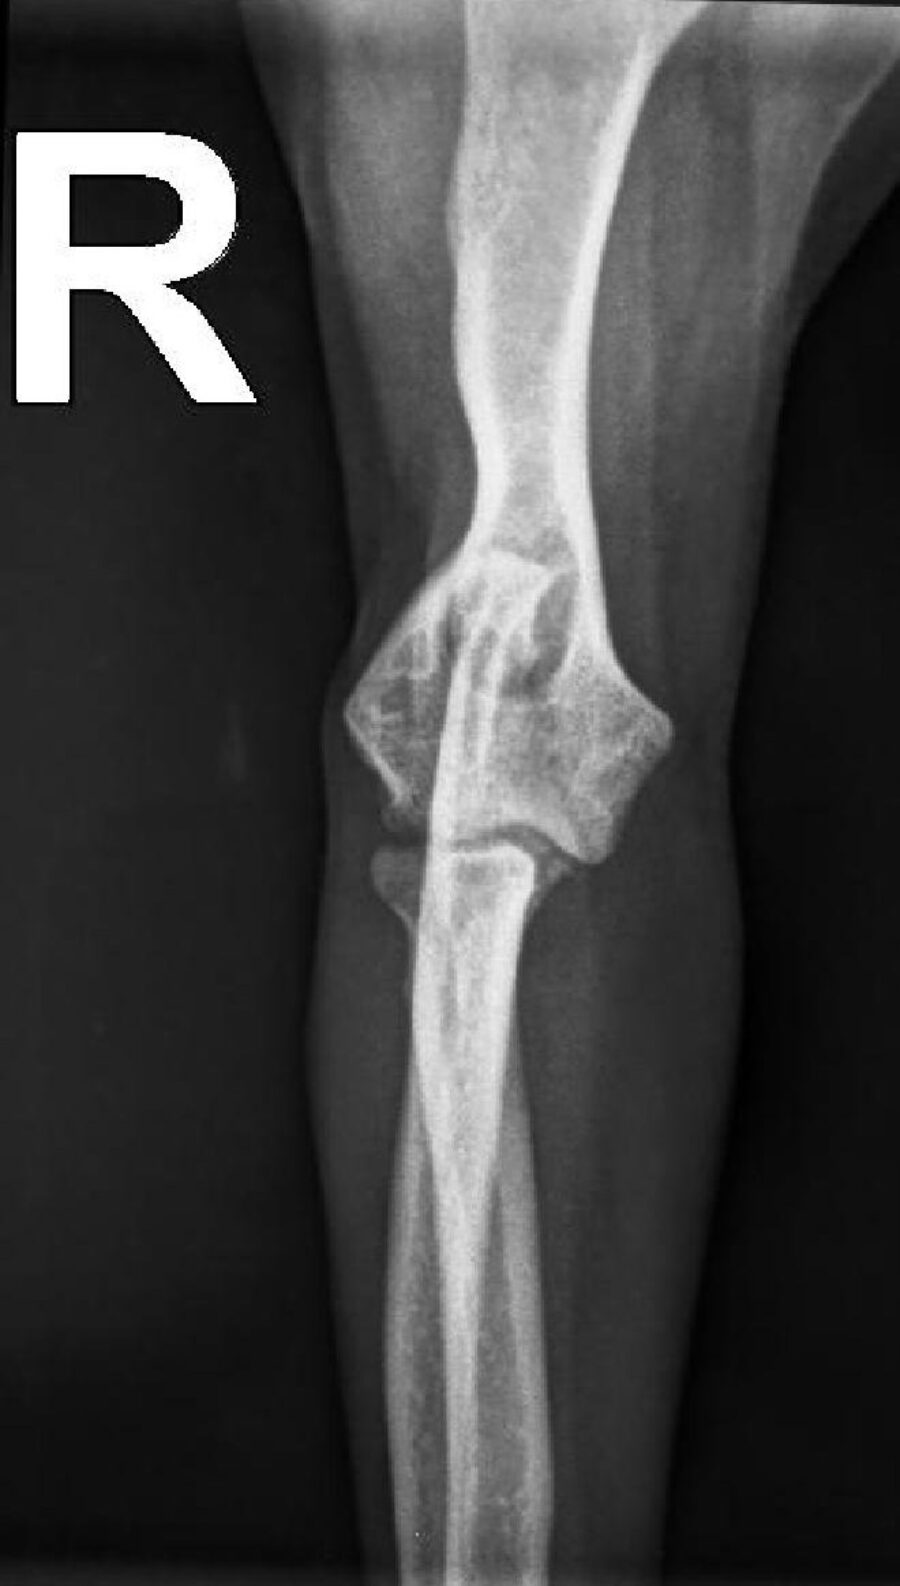

• Fracturen met platen, schroeven of pinnen

• Een te losse knieschijf opereren (patella luxatie)

• Kruisbandoperatie